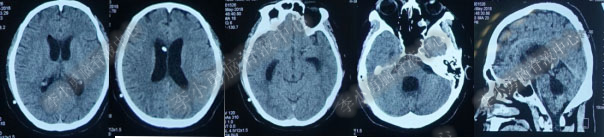

2017年6月27日(分流术后5天),复查头部CT(图-6)显示幕上脑室及第四脑室均有所缩小。

图-6:2017年6月27日头部CT

图-7:2017年7月30日头部CT

图-8:2017年9月18日头部CT

图-9:2017年10月15日头部CT